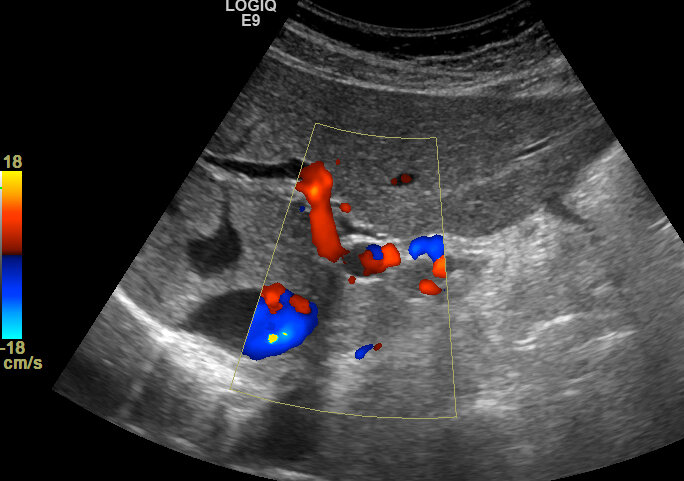

При ультразвуковом исследовании печени врач УЗД визуализирует гепатикохоледох. Зона слияния правого и левого внутрипеченочных протоков, как правило, не визуализируется, но при отсутствии расширения протоков визуализация этой зоны не имеет принципиального значения. Но иногда можно увидеть отчетливо слияние правого и левого внутрипеченочных протоков. Видео: https://dzen.ru/video/watch/66582ab24576313e323ff93d Убедиться, что это именно протоки, а не сосуды, можно при цветной допплерографии - просвет протоков не окрашивается. Видео: https://dzen.ru/video/watch/66582b051b8759059da23b61 Следует отметить, что с точки зрения анатомии, правильнее говорить не "бифуркация" а "конъюнкция", поскольку имеет место не разделение одного протока на два, а слияние двух в один.

Убедиться, что это именно протоки, а не сосуды, можно при цветной допплерографии - просвет протоков не окрашивается.